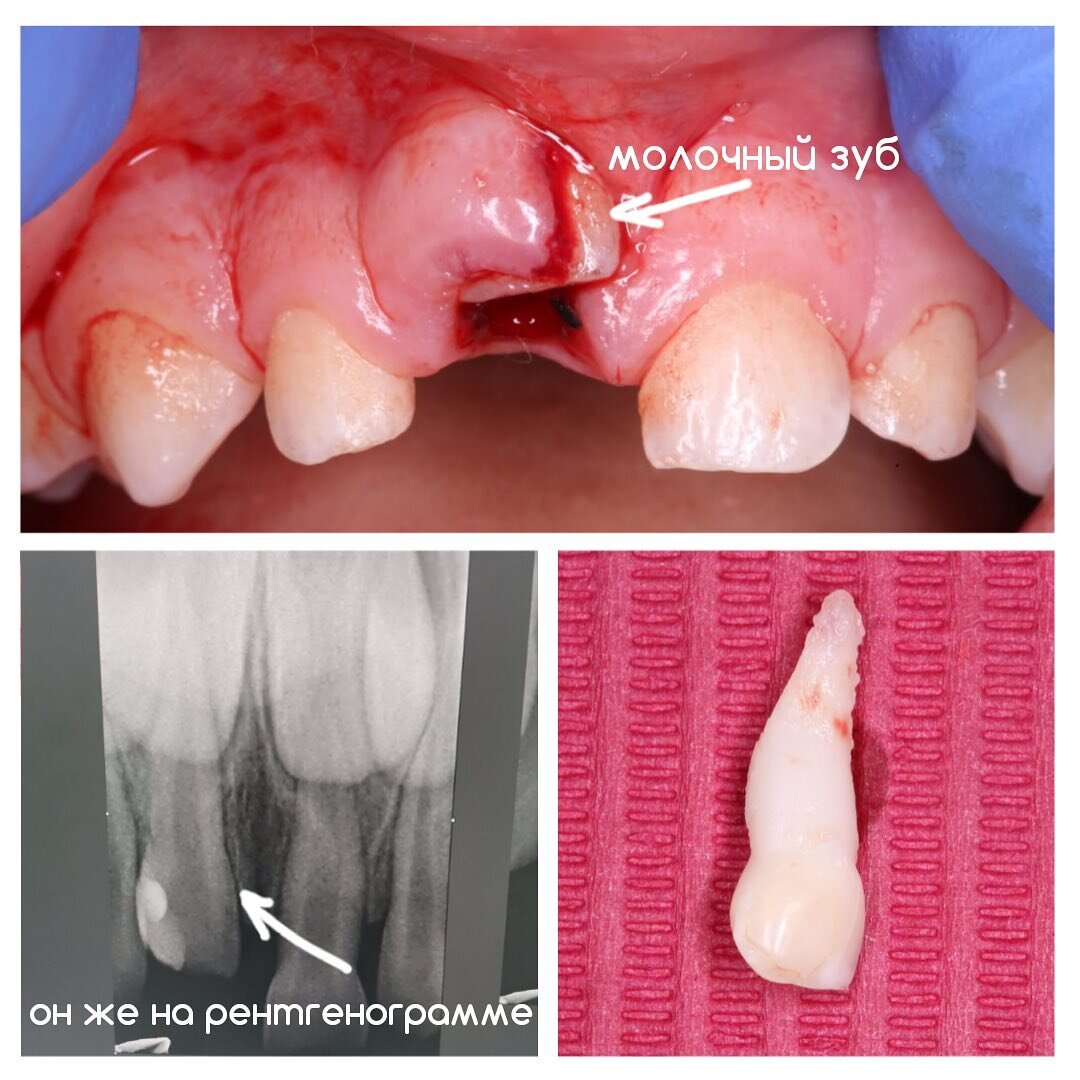

Во время карантина дети находят себе активные развлечения даже дома. Риск травмы зубов по-прежнему актуален. Поэтому #ЦентрСелютиной работает в режиме оказания экстренной и неотложной помощи. Как раз вот для таких случаев, как на фото. Так выглядит острая травма зуба, которая называется вколоченный вывих. Да, такое тоже может случиться. Ребенку 3 года. Упал и ударился об металл на детской площадке. Родители не медля примчались в #ЦентрСелютиной. Но, к сожалению, зуб спасти не удалось. ✔Вколоченный вывих - это когда при вертикальном травматическом воздействии происходит углубление или вколачивание зуба в альвеолу с повреждением тканей пародонта. Высота вколоченного зуба заметно укорачивается, а у пациента наблюдаются сильные болевые ощущения. При вколоченном вывихе в большинстве случаев зуб оставляется под наблюдение. Молочный зуб со временем может вернуться на место и у него есть все шансы дослужить ребёнку до момента смены. Постоянный же можно попытаться вернуть на место, шинирова

Так выглядит острая травма зуба, которая называется вколоченный вывих.

Ребенку 3 года.

Упал и ударился об металл на детской площадке.

Но, к сожалению, зуб спасти не удалось.

✔Вколоченный вывих - это когда при вертикальном травматическом воздействии происходит углубление или вколачивание зуба в альвеолу с повреждением тканей пародонта.

Высота вколоченного зуба заметно укорачивается, а у пациента наблюдаются сильные болевые ощущения.

В нашем случае молочный зубик почти полностью ушел вглубь тканей десны и спасти его не удалось.